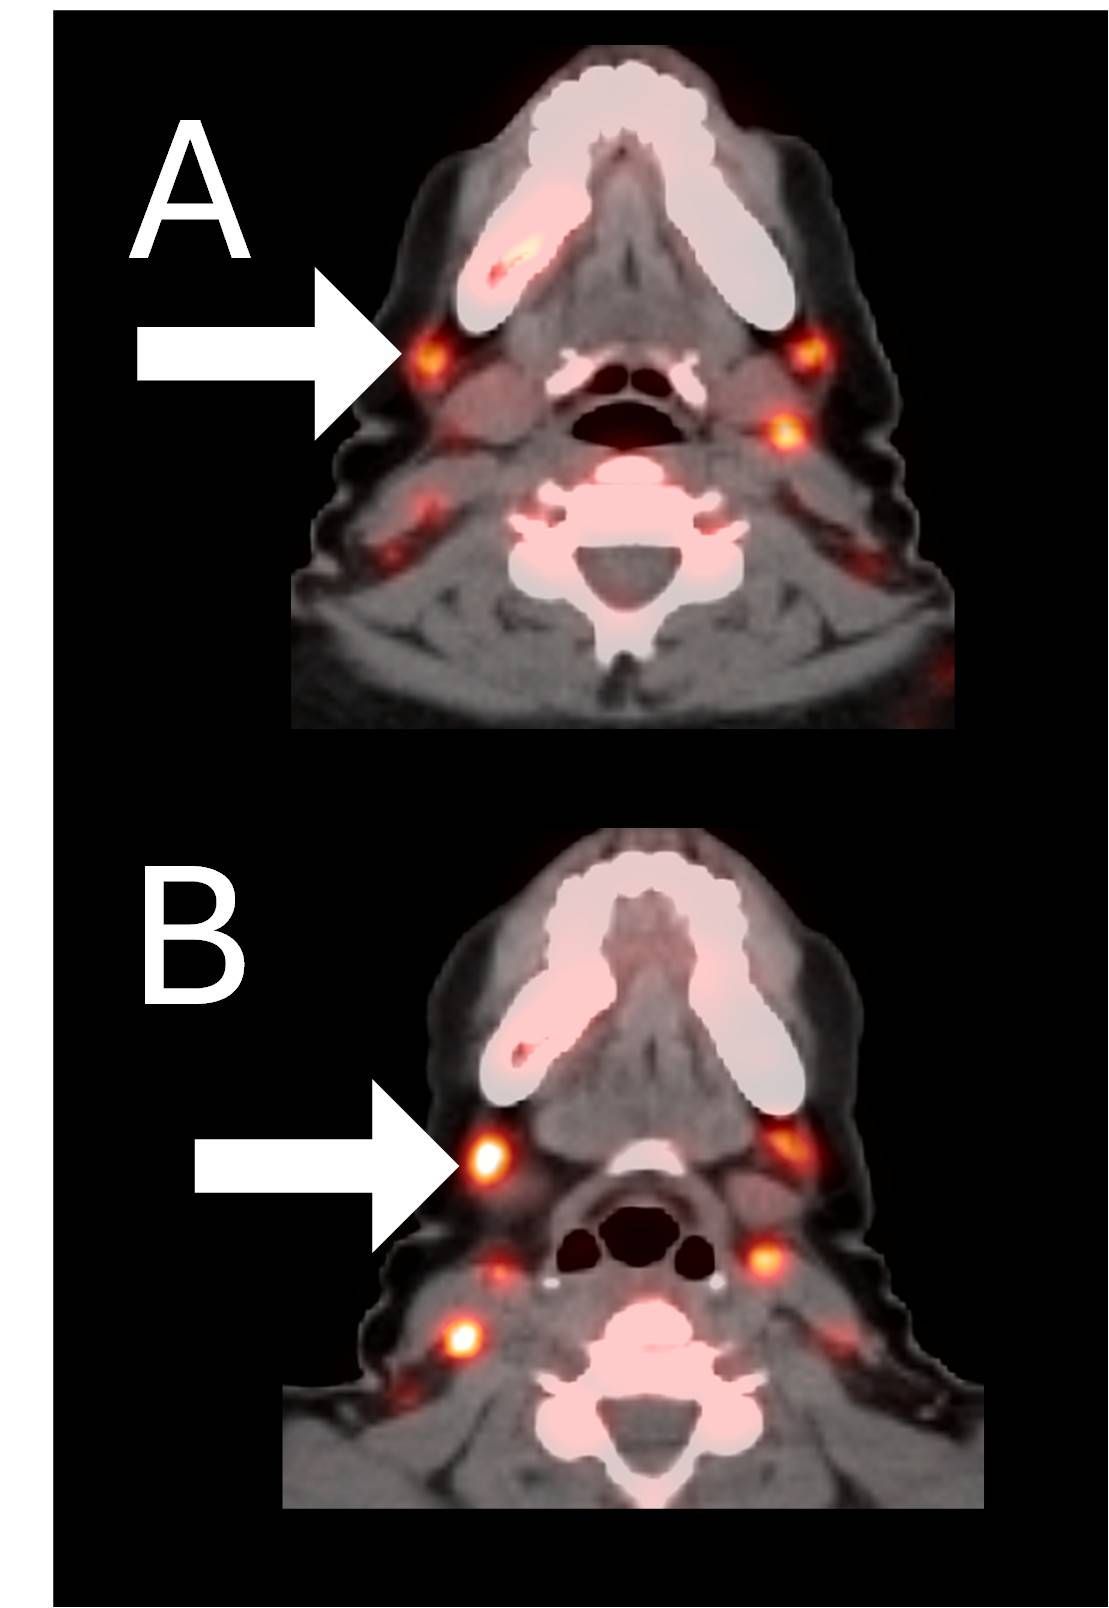

Before BriaCell Treatment Image A: CD8 ImmunoPET image

Pre-treatment imaging of cervical (neck) lymph nodes with moderate uptake indicating presence of some CD8+ cytotoxic ("killer") T cells.

After BriaCell Treatment Image B: CD8 ImmunoPET image

Post treatment enhancement of cervical (neck) lymph nodes indicating immune system activation and increased presence of CD8+ cytotoxic T cells.

Example 2 Images (Patient 15-005): CD8 ImmunoPET images pre (A) and post (B) Bria-IMT treatment